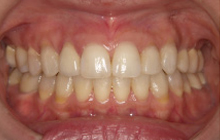

(治療後:写真右)

矯正治療をおこない歯列を整え、金属の詰め物はセラミッククラウンに換えて咬み合わせを再構成しました。

三本の小臼歯を抜歯していますが、歯並びを小さくしないようにしています。

そして矯正治療後、初診時の様々な訴えは解消しました。